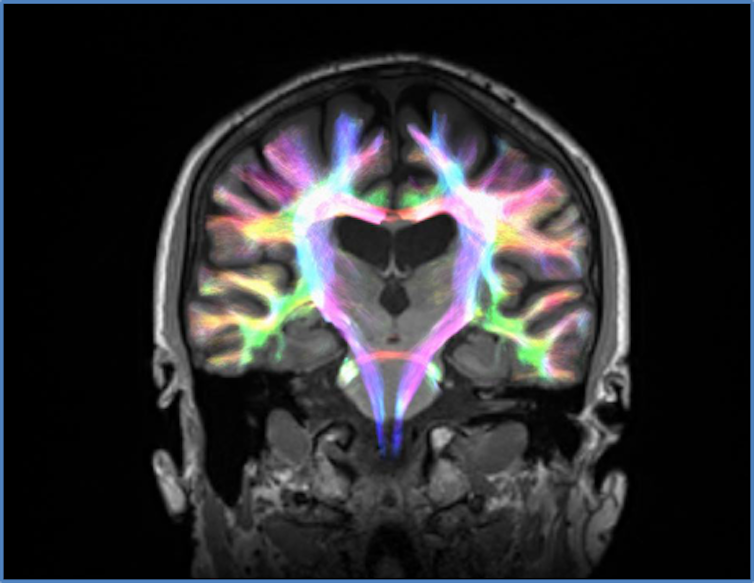

We used an advanced method of brain imaging called diffusion MRI, which allowed us to visualise the structure of connections between the different brain regions involved in these circuits. Using this technology, we could quantify if the strength of these connections had been affected by Parkinson’s disease.

We took a group of 57 people with Parkinson’s disease on dopaminergic medication and focused on two brain networks thought to be crucial for decision making: a network for choosing the best course of action and a network for stopping inappropriate actions. These networks connect regions of the brain within the frontal lobes, an area known to support higher-order features of personality such as judgement.